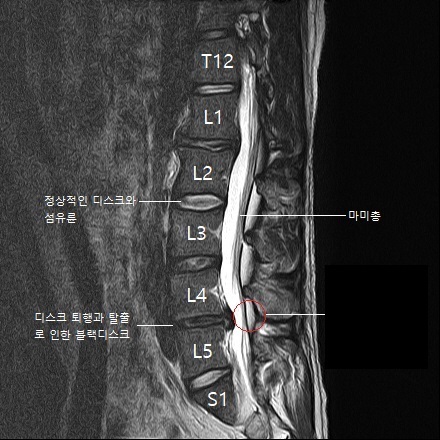

척추와 뼈 사이에 위치한 이 디스크는 외부로부터의 물리적 충격을 완화하고 단단한 뼈가 직접 충돌할 때 문제가 발생하지 않도록 하는 탄성이 높은 구조입니다. 외부의 영향이나 잘못된 위치로 인해 디스크가 꺼지면 염증이 발생하고 신경이 눌려 요통과 요통이 발생합니다. 기술적으로는 요추 디스크 분리라고 하며 일반적으로 요추 디스크 고장이라고 합니다.

디스크는 몸이 척추로부터 떨어져 많은 고통을 느낄 때까지 여러 단계를 거칩니다.